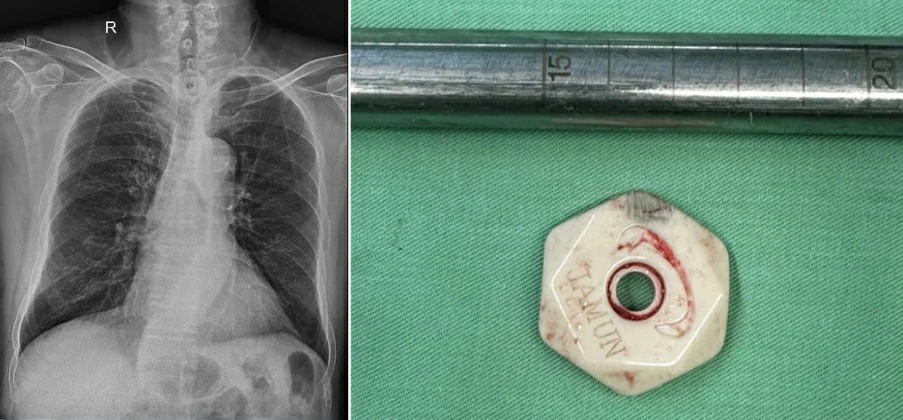

Hình ảnh dị vật cản quang trên phim Xquang ngực thẳng và dị vật sau khi được lấy ra khỏi cơ thể bệnh nhân.

Theo thông tin từ kíp trực, sau khi thăm khám lâm sàng, thực hiện các phương tiện chẩn đoán hình ảnh và hội chẩn khẩn cấp, các bác sĩ xác định có dị vật mắc tại thực quản đoạn tương ứng mức đốt sống ngực D1-D2. Ngay trong đêm, các bác sĩ chuyên khoa Tai Mũi Họng đã phối hợp với ê kíp gây mê hồi sức tiến hành nội soi thực quản ống cứng cấp cứu dưới gây mê nội khí quản.

Dị vật được xác định là một khối đá màu trắng, hình lục giác, các góc được mài nhẵn, đường kính khoảng 3 cm, nằm trong thực quản, vị trí cách cung răng trên khoảng 24 cm. Dị vật đã được lấy ra an toàn bằng dụng cụ chuyên dụng. Tuy nhiên do kích thước dị vật lớn, quá trình di chuyển trong lòng thực quản, đặc biệt khi bệnh nhân có động tác khạc nhổ nhằm tống dị vật ra ngoài, đã gây tổn thương niêm mạc thực quản, dẫn đến trầy xước và chảy máu. Sau khi kết thúc thủ thuật, kíp trực đã tiến hành đặt sonde dạ dày để nuôi ăn và theo dõi bệnh nhân.